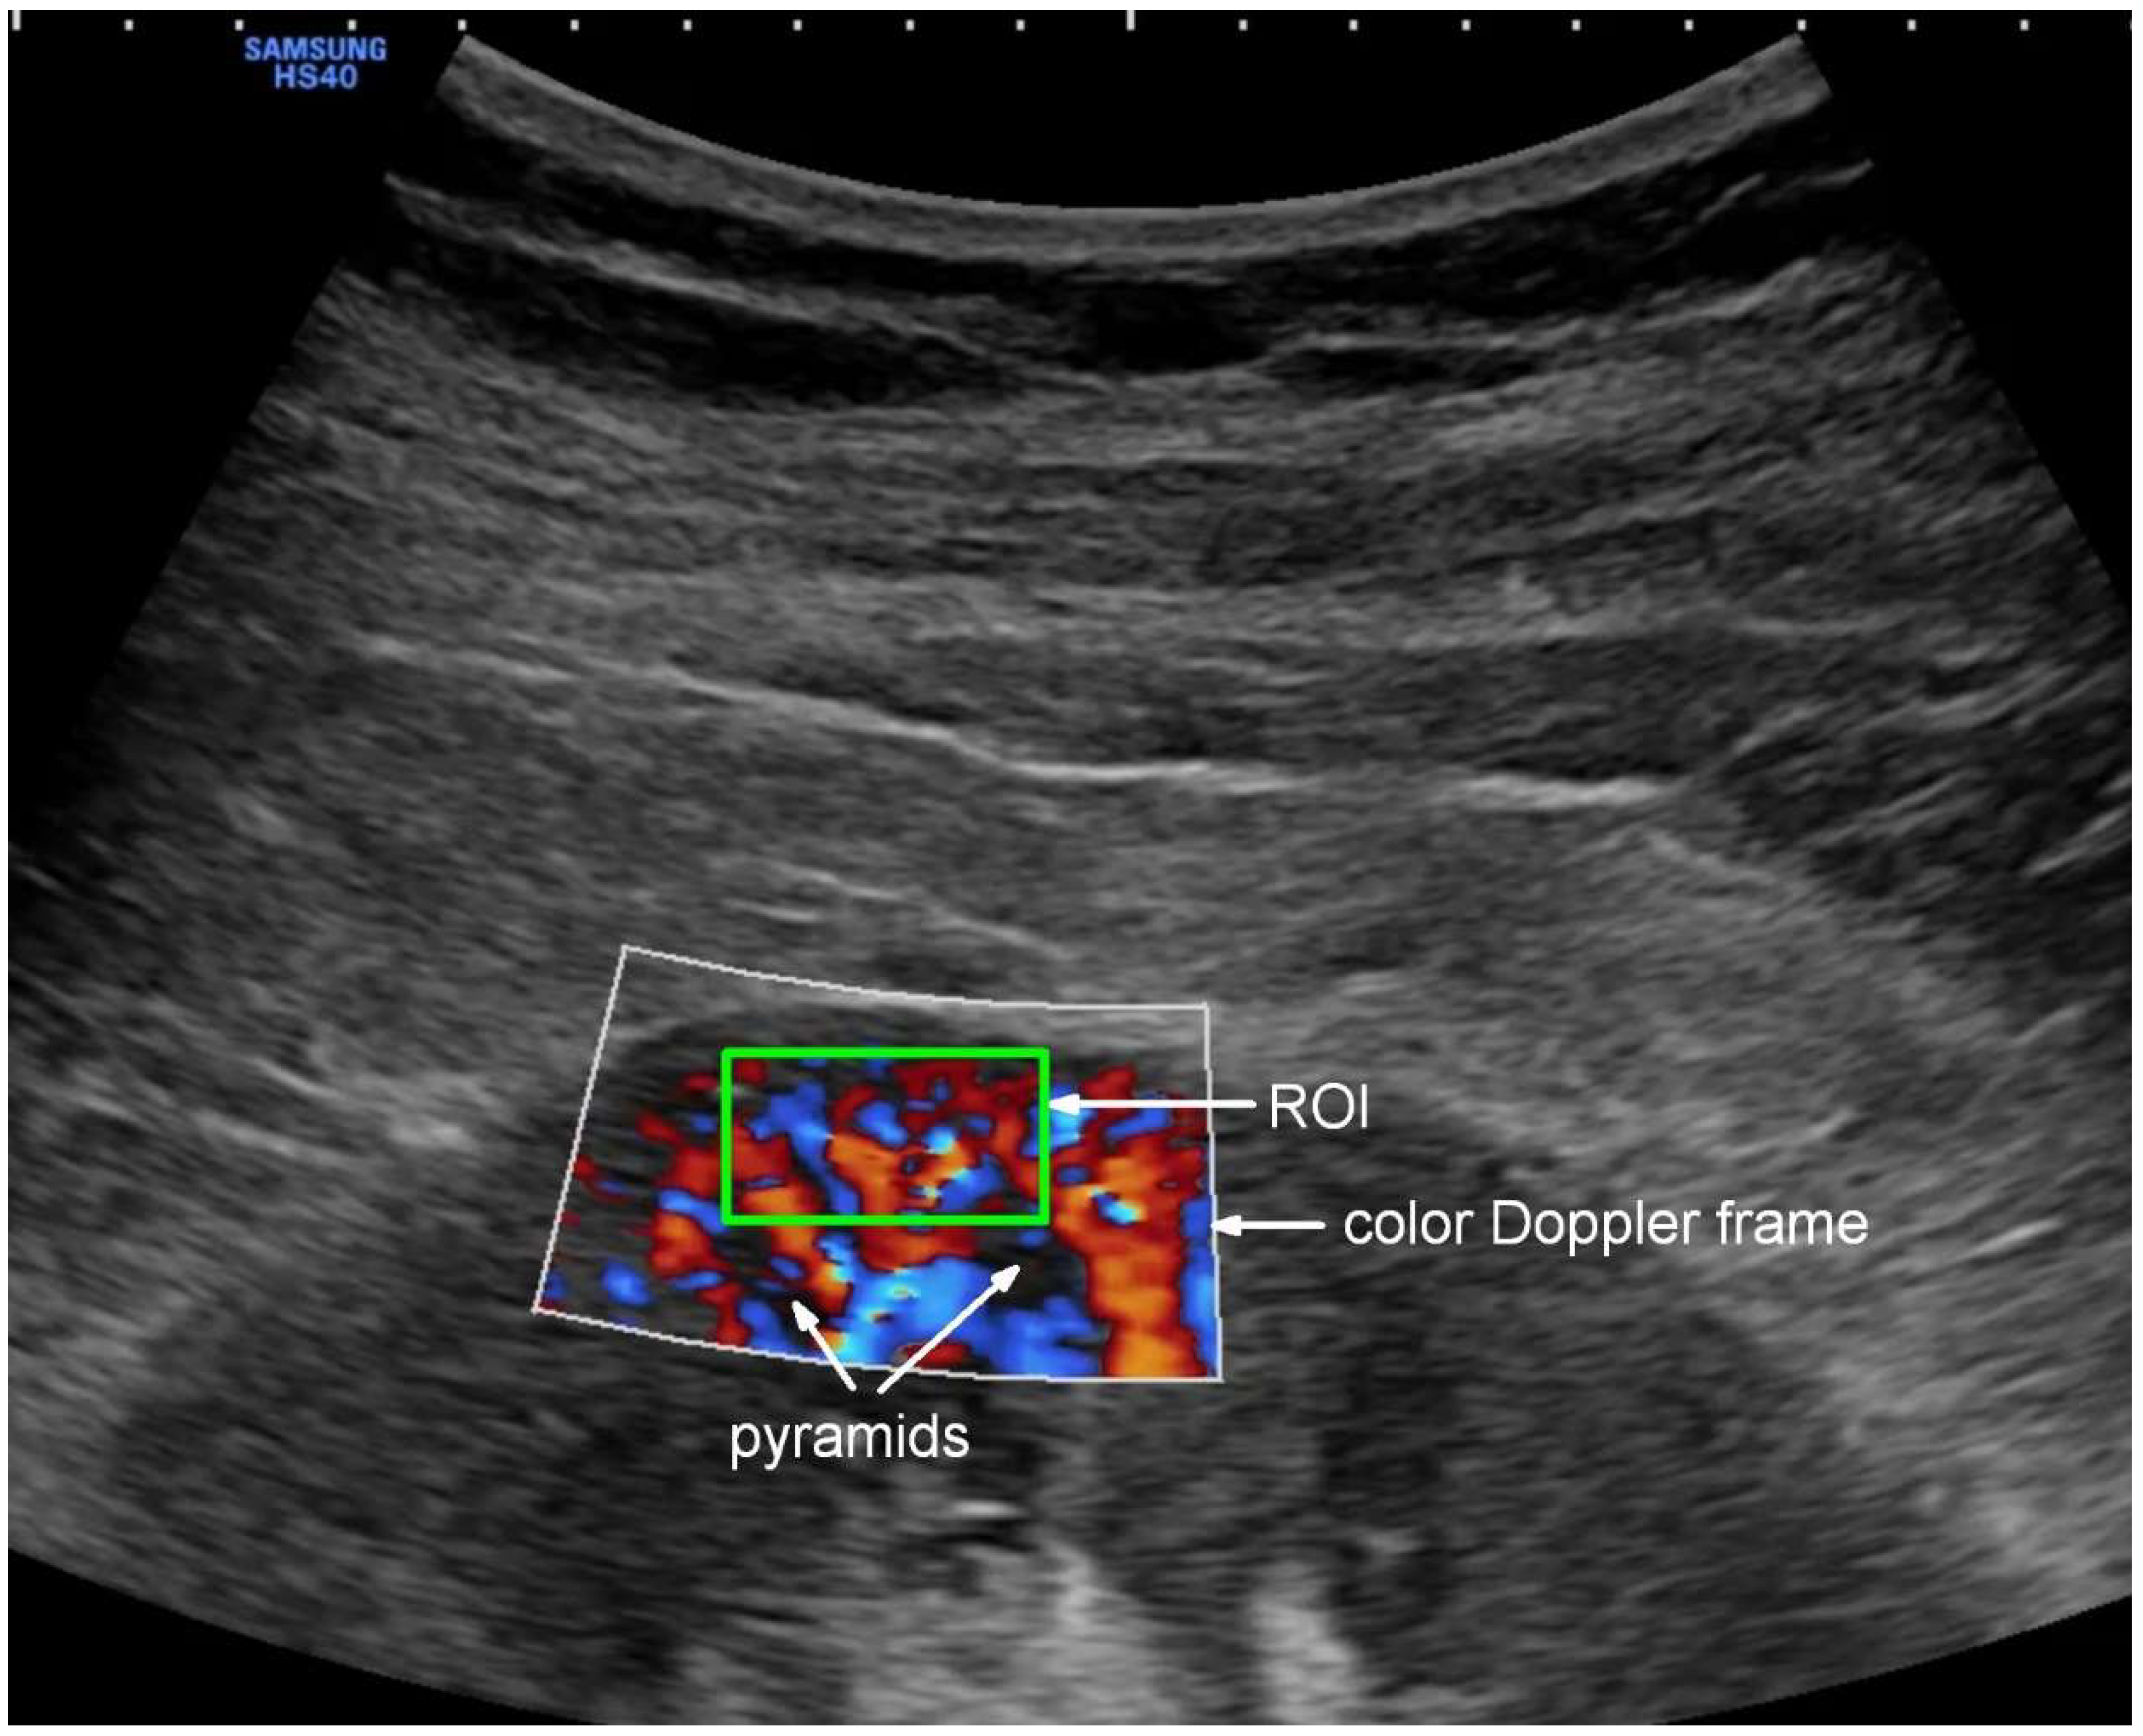

2.5. Ultrasound Examination

- Scholbach, T.; Dimos, I.; Scholbach, J. A New Method of Color Doppler Perfusion Measurement via Dynamic Sonographic Signal Quantification in Renal Parenchyma. Nephron Physiol. 2004, 96, 99–104. [Google Scholar] [CrossRef]

- Scholbach, T. Dynamic Tissue Perfusion Measurement—Basics and Applications. In Sonography; Thoirs, K., Ed.; InTech: London, UK, 2012; ISBN 978-953-307-947-9. [Google Scholar]

- Scholbach, T.M.; Vogel, C.; Bergner, N. Color Doppler Sonographic Dynamic Tissue Perfusion Measurement Demonstrates Significantly Reduced Cortical Perfusion in Children with Diabetes Mellitus Type 1 without Microalbuminuria and Apparently Healthy Kidneys. Ultraschall Der Med. 2014, 35, 445–450. [Google Scholar] [CrossRef]

- Lubas, A.; Zegadło, A.; Frankowska, E.; Klimkiewicz, J.; Jędrych, E.; Niemczyk, S. Ultrasound Doppler Flow Parameters Are Independently Associated with Renal Cortex Contrast-Enhanced Multidetector Computed Tomography Perfusion and Kidney Function. J. Clin. Med. 2023, 12, 2111. [Google Scholar] [CrossRef]